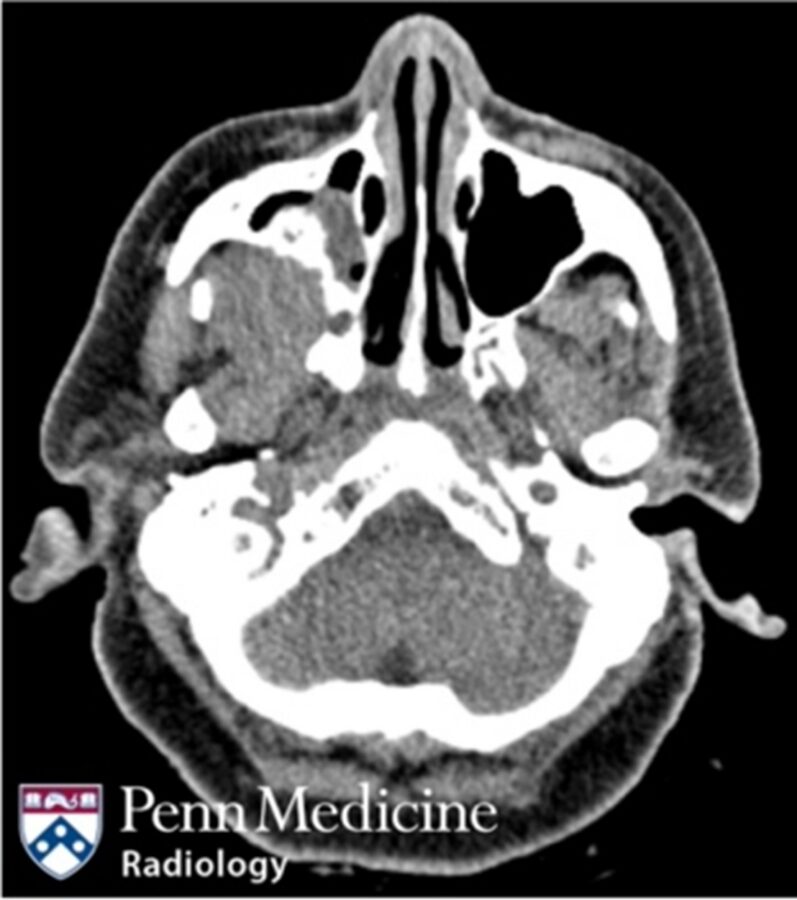

52-year-old woman with vertigo and sinus congestion

A 52-year-old female presented to the emergency department for vertigo and sinus congestion.

Published Date: February 5, 2026

Tags:

CT

,

Head and Neck

MRI

PET